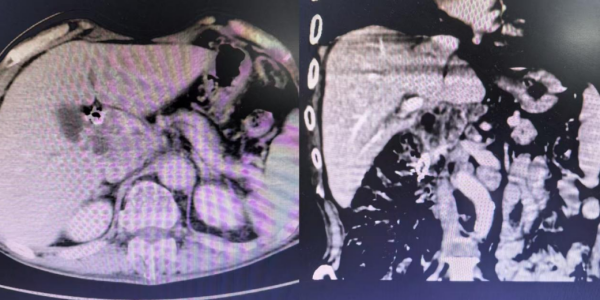

患者胆总管受压,肝内胆管重度扩张

整个手术过程一气呵成,成功开通了梗阻的胆道。手术创口小,患者术后恢复快,全身皮肤及巩膜黄染明显消退,食欲显著好转,精神状态恢复,体重也有所增加,日常生活实现自理。复查CT显示胆道梗阻解除,胆道支架及碘125粒子条位置良好。

胆道支架植入后胆道梗阻解除

胆总管支架术后改变,肝内胆管无明显扩张